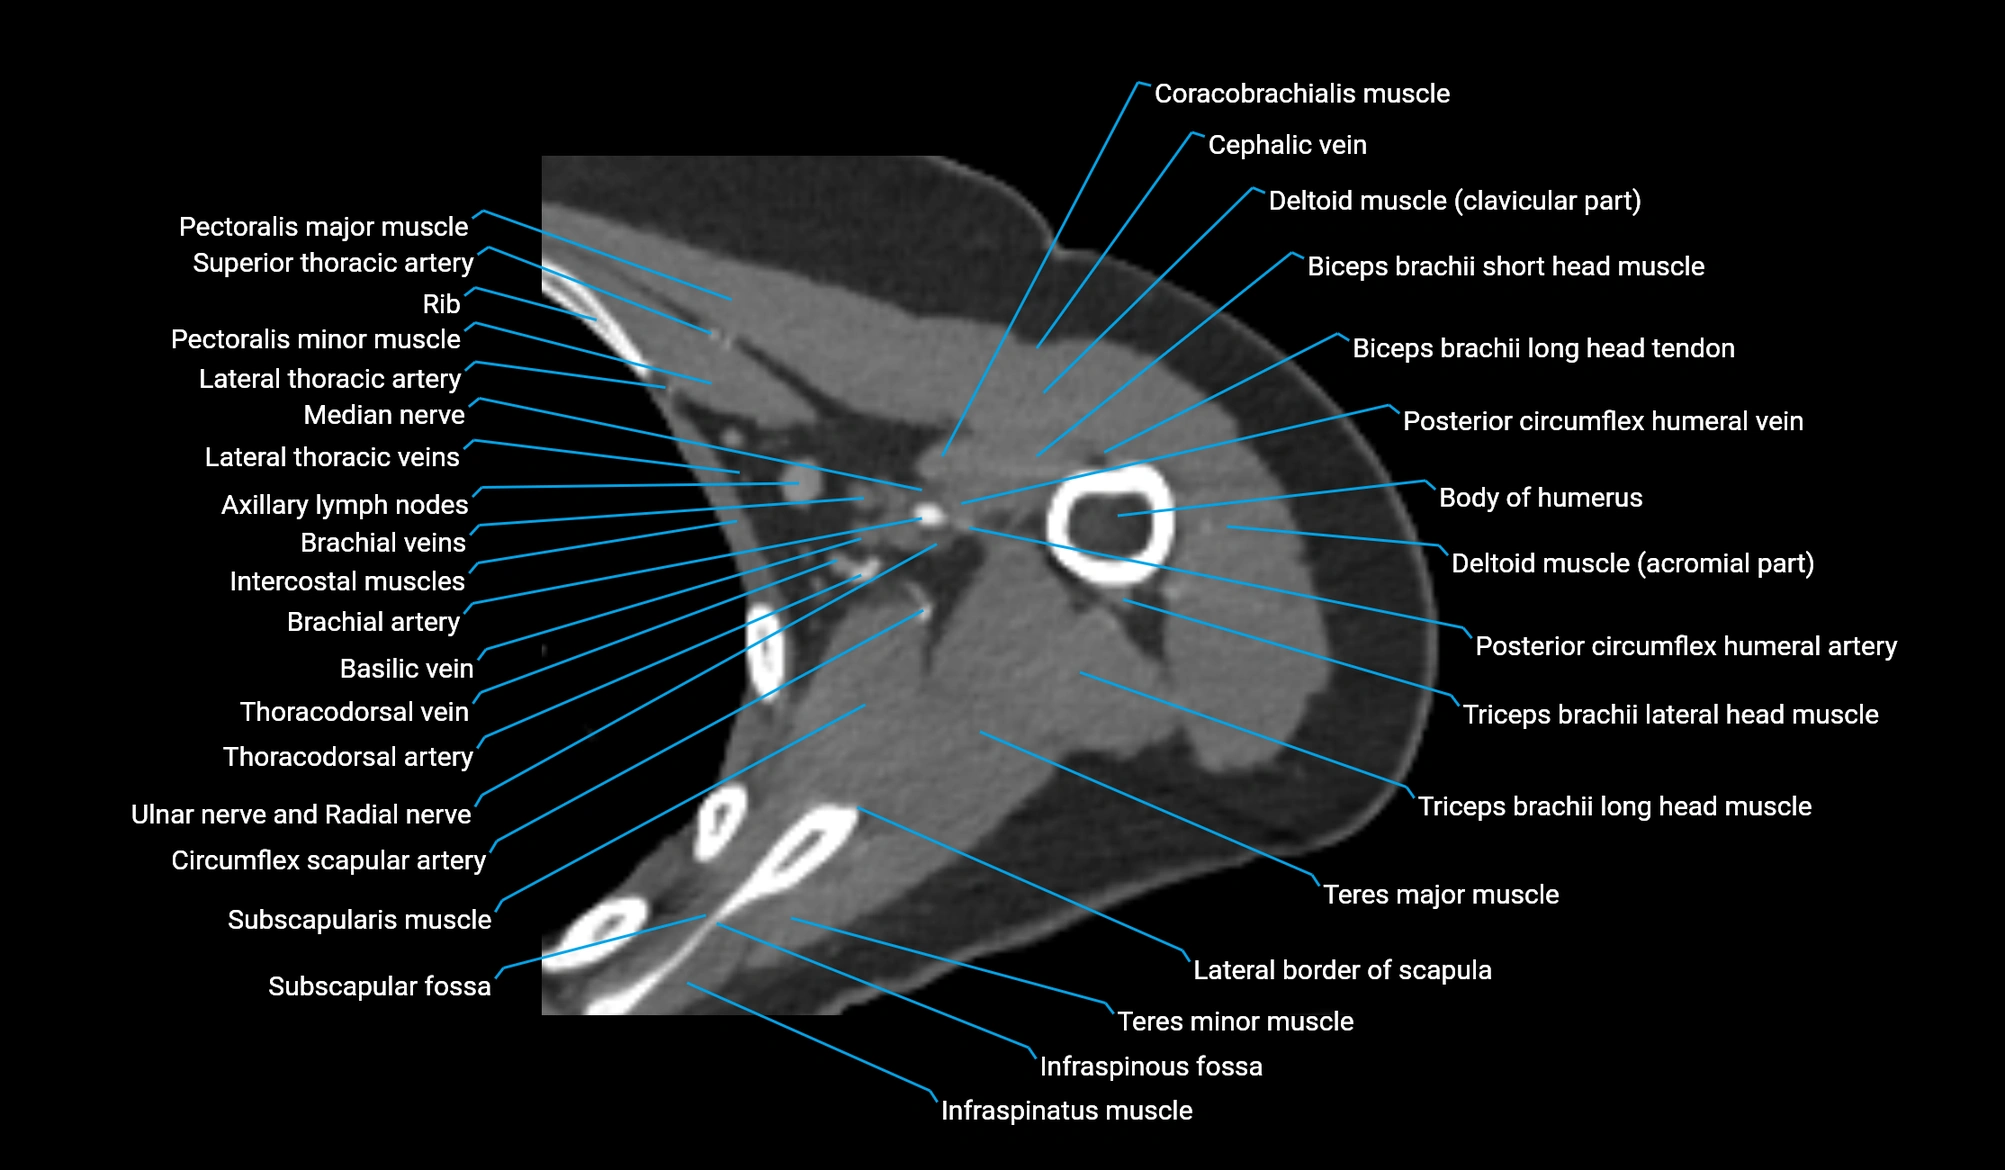

CT image